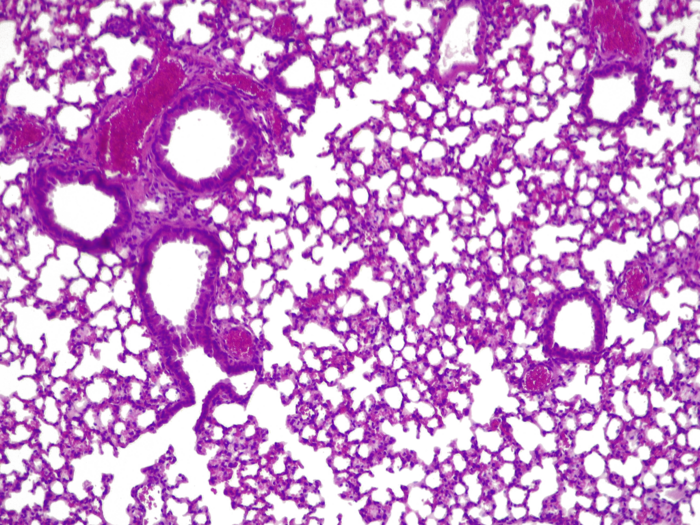

image: This shows a cross-section of a mouse lung infected with Pseudonomas aeruginosa. The mouse was treated with a version of Mycoplasma pneumoniae that is able to produce therapeutic molecules such as pyocins specifically-designed to combat P. aeruginosa. This therapeutic version of M. pneumoniae acts like a ‘living medicine’ reducing the effects of the infection and preserving air in the alveoli. view more

El equipo científico observó que el uso del tratamiento en ratones redujo significativamente las infecciones pulmonares. La "píldora viva" duplicó la tasa de supervivencia del ratón en comparación con la opción de no usar ningún tratamiento. La administración de una única dosis alta del tratamiento no mostró signos de toxicidad en los pulmones. Una vez que el tratamiento hubo terminado su curso, el sistema inmune innato eliminó las bacterias modificadas en un período de cuatro días.